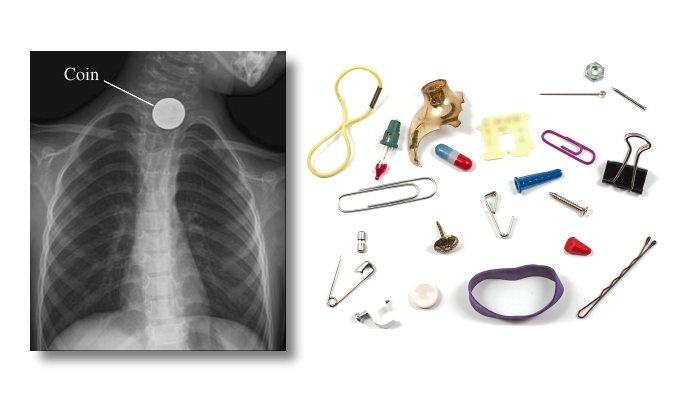

قد يكون ما تعاني منه سببه وجود جسم غريب عالق في حلقك كعظمة سمك مثلا ، و هذه الحالة تعد من الحالات الطارئة التي ننصحك فيها بشدة بالمتابعة الطبية الفورية